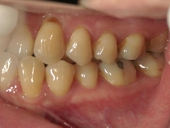

矯正歯科 治療前 左